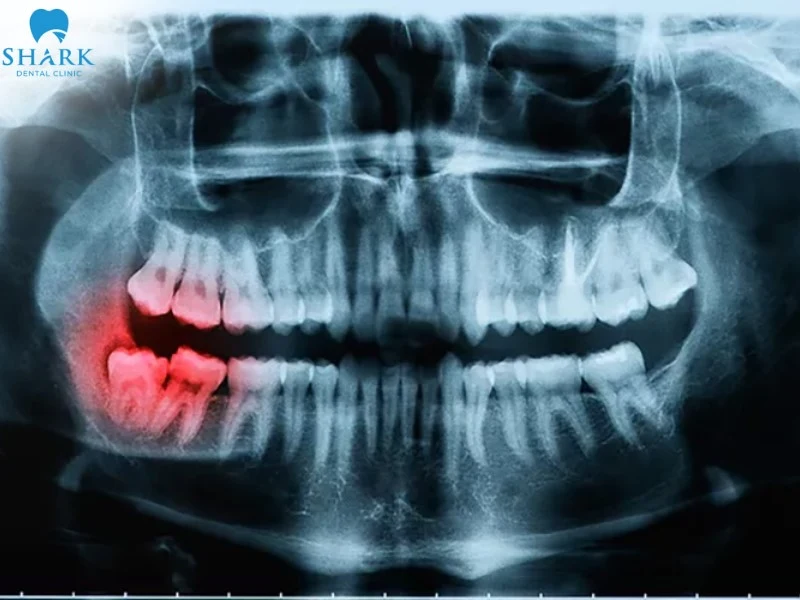

Chụp Panorama răng là kỹ thuật sử dụng tia X để chụp lại toàn bộ khung hàm, bao gồm răng, xương hàm trên, xương hàm dưới và các cấu trúc lân cận chỉ trên một tấm phim duy nhất.

Khác với các phim X-quang nhỏ chỉ chụp được 1-2 răng, chụp phim răng Panorama mang lại góc nhìn 2 chiều (2D) toàn diện, giúp bác sĩ quan sát được những vùng mà mắt thường hoặc phim chụp thông thường không thể thấy được.

- Phát hiện bệnh lý ẩn: Nhận diện sớm các nang chân răng, u men xương hàm, áp xe quanh chóp hoặc sâu răng ở kẽ khuất.

Nhổ răng khôn

Răng khôn thường mọc lệch, mọc ngầm hoặc đâm vào răng số 7. Phim Panorama cho thấy rõ vị trí chân răng, độ nghiêng của răng và đặc biệt là khoảng cách từ chân răng đến dây thần kinh ống hàm dưới, giúp ca nhổ răng diễn ra an toàn, tránh biến chứng tê môi má.